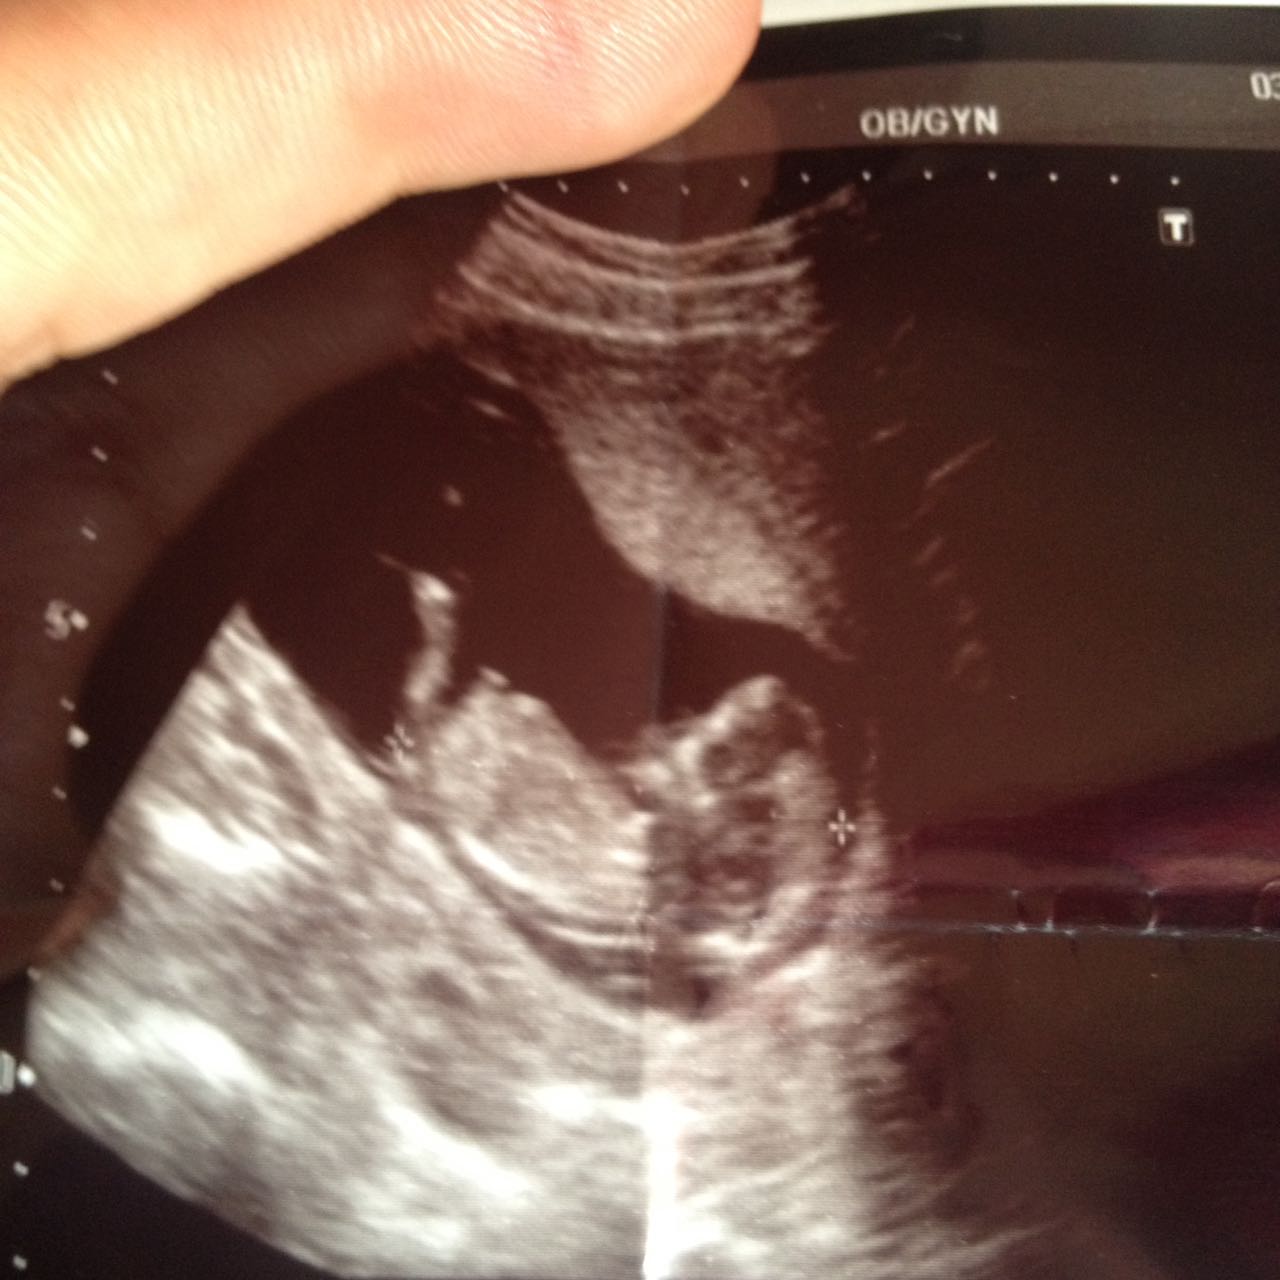

Merhaba alya hanım.Sizin görselde nub çıkıntısı var fakat , uç kısım yalnız flu .Bu yüzden emin olmamakla birlikte bebeğin cinsiyeti kız gibi görünüyor.

Mrb 12+3 gunluk hamileyim rica etsem nub teorisine göre cinsiyet tahmini verebilir misiniz ilk bebegim sağlıklı olsun ama çok merak ediyorum dr henüz erken dedi